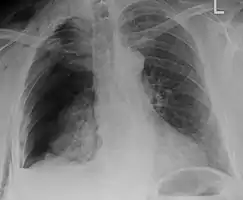

Plain X-rays often pick up displaced fractures but often miss undisplaced fractures.[13] CT scanning is generally able to pick up both types of fractures.[13]

Right sided pneumothorax and rib fractures